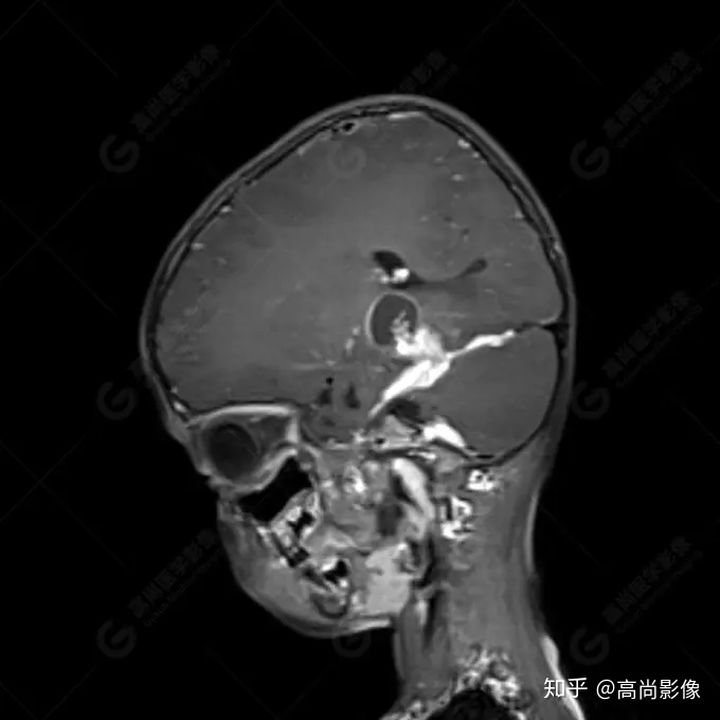

右側(cè)顳葉腫瘤切除術(shù)后(具體不詳):右側(cè)顳部骨質(zhì)不連續(xù)呈術(shù)后改變,右側(cè)顳葉術(shù)區(qū)見片狀長T1長T2信號影,F(xiàn)LAIR呈低信號;術(shù)區(qū)后方右側(cè)顳枕葉見一巨大占位性病變影,邊界欠清,大小約6.2×5.8×4.3cm(前后×左右×上下),信號不均勻,T1WI呈等稍低信號間雜少許高信號,T2WI呈高稍低混雜信號,DWI示部分病灶彌散受限,相應(yīng)ADC圖減低,磁敏感序列見部分呈極低信號,增強(qiáng)掃描可見明顯不均勻強(qiáng)化,鄰近硬腦膜及小腦幕增厚并明顯強(qiáng)化;另延髓右前方及右側(cè)橋小腦角區(qū)見一不規(guī)則形異常信號影,大小約3.2×1.3×3.7cm(左右×前后×上下),呈長T1稍長T2信號,F(xiàn)LAIR呈等信號,DWI未見受限,增強(qiáng)后明顯均勻強(qiáng)化,鄰近腦膜明顯強(qiáng)化。鄰近腦實質(zhì)及右側(cè)顳角明顯受壓;左側(cè)大腦半球未見局灶性信號異常,中線結(jié)構(gòu)稍左移。

右側(cè)顳葉腫瘤切除術(shù)后:現(xiàn)術(shù)區(qū)后方右側(cè)顳枕葉及延髓右前方占位,右側(cè)顳枕部硬腦膜及小腦幕明顯強(qiáng)化,結(jié)合既往影像資料,考慮為胚胎源性惡性腫瘤,如非典型畸胎樣/橫紋肌樣瘤(AT/RT)或原始神經(jīng)外胚層腫瘤(PNET)。

術(shù)后隨訪病理結(jié)果:非典型畸胎樣/橫紋肌樣瘤。